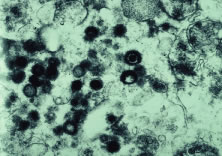

Both herpes simplex virus type 1 and herpes simplex virus type 2 (HSV-1, HSV-2) may cause ARN.20–22 In a single report, CMV particles were identified in and cultured from the retina of an enucleated eye of a nonimmunosuppressed patient suffering from bilateral ARN.23 VZV has been reported most frequently as the viral etiologic agent of ARN.2,3,24–27 We have demonstrated herpesvirus family viral particles in endoretinal biopsy specimens taken from patients in the active stage of the disease who showed an enormous viral load (Fig. 4). These studies, combined with the failure of many enucleated eyes with ARN to demonstrate evidence of viral particles, indicate that the virus is present only in the active stages of the disease and that a gliotic retina will not demonstrate the etiologic agent.28

Light microscopic examination of these retinas reveals full-thickness necrosis and loss of the retinal architecture.25,30,35 Within the necrotic retina, macrophages, plasma cells, and other inflammatory cells are found in addition to cells containing eosinophilic inclusions. There is a sharp demarcation between affected and nonaffected retina, suggesting cell-to-cell transmission of the virus. Arteritis manifests as endothelial cell swelling with occlusion of the vessel lumen, infiltration of the subendothelium with plasma cells, and inflammatory cell thrombi. When healing occurs, a thin glial scar replaces the necrotic neural elements. Herpesvirus capsids may be observed in electron microscopic specimens of actively infected retinal tissue but are not seen once healing has occurred and glial scar tissue replaces the necrotic retina.28,30